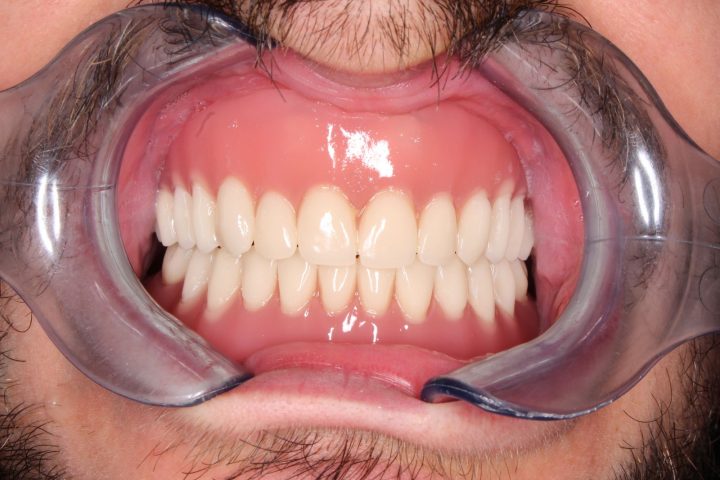

Mark ist ein englischer Patient bei uns, der sich in seinem ganzen Leben nach weißen Zähnen gesehnt hat. Sein Fall ist unregelmäßig, weil er früher eine andere ungarische Zahnklinik besucht, hat, wo er Implantate bekommen hat. Aber er war mit der Patientbetreuung nicht zufrieden.

Auf den Rat von seinem Freund hat er so entschieden, dass er die Behandlung in der Zahnklinik Centrocc Dental beenden möchte. Er hat diese Entscheidung nicht bereut, und hat die Klinik seinen alten Traum verwirklicht.

Auf seine Implantate haben wir durch Frau Dr. Erdélyi insgesamt 24 Stück Metallkremaik Kronen bearbeitet.